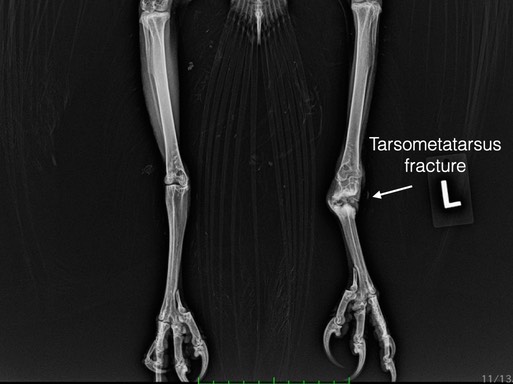

There were just seven admissions this past week, all but one a raptor. Of four Great Horned Owls, three had humerus fractures, the fourth was tangled in a fence, none could be saved. A Sharp-shinned Hawk was shot and a Red-tailed Hawk was likely struck by a vehicle. Neither could be saved. Living in a world filled with humans is no easy task for wildlife.

Great Horned Owl 21-761